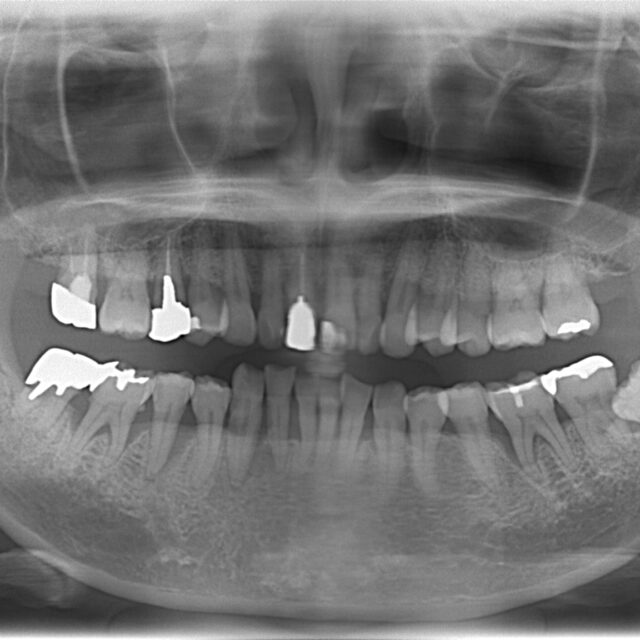

歯周病